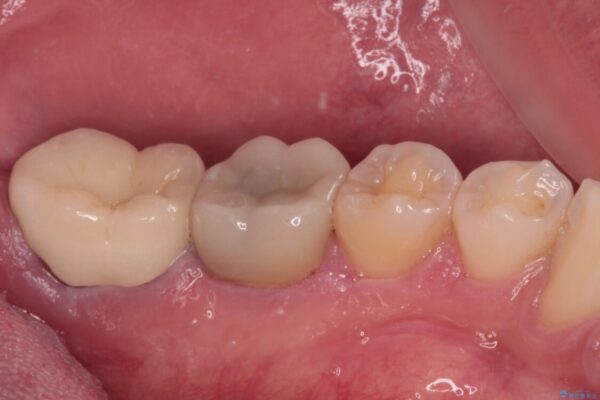

治療前

• 海外赴任前に治したい 割れてしまった奥歯のオールセラミッククラウン 治療前画像

間もなく海外赴任という状況で奥歯のクラウンが割れてしまったとのことで来院された患者様です。

下顎の1番奥の歯であり、歯肉に覆われている部分が大きいためセラミックの十分な厚みが取れない状態でした。

強化セラミックを用いたオールセラミッククラウンにて補綴治療を行うこととしました。